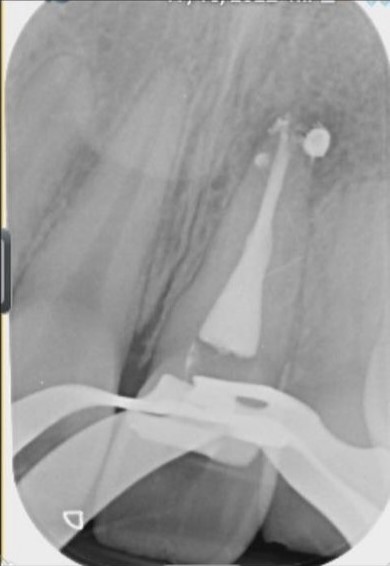

• Obturation des canaux : Une fois les canaux radiculaires nettoyés, ils sont remplis d’un matériau d’obturation avec un ciment spécifique pour assurer l’étanchéité et empêcher la réinfection.

L’inflammation se trouve au cœur de la pulpe dentaire. Quand celle-ci est atteinte, le traitement endodontique est idéal. Il permet d’accéder à la pulpe, d’éliminer ce tissu vascularisé et innervé et de désinfecter les canaux en profondeur, de les sceller ensuite (obturation).

Une fois les canaux nettoyés et désinfectés, une obturation canalaire est mise en place pour assurer l’étanchéité et éviter la réapparition de l’infection. Dans certains cas, une couronne dentaire ou une prothèse est nécessaire pour restaurer la dent après le traitement.

Le processus consiste à nettoyer et obturer l’intérieur de la dent afin d’éliminer toute infection et de protéger sa structure.